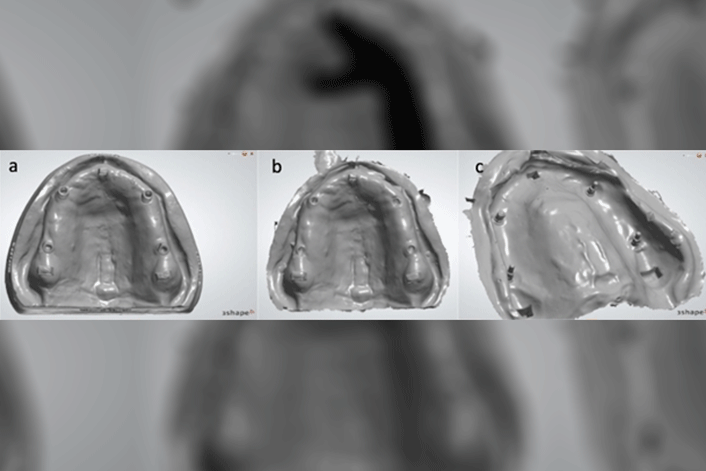

An edentulous maxillary polymerized PMMA 3D-printed resin model with three built-in landmarks was prepared and four implants with internal connections were placed and positioned according to the all-on-four treatment design. The study evaluated and compared the accuracy (precision and trueness) of the digital intraoral scan of the model using a Trios 3 intraoral scanner, and scan bodies and a conventional open tray impression that was digitized using the same scanner.